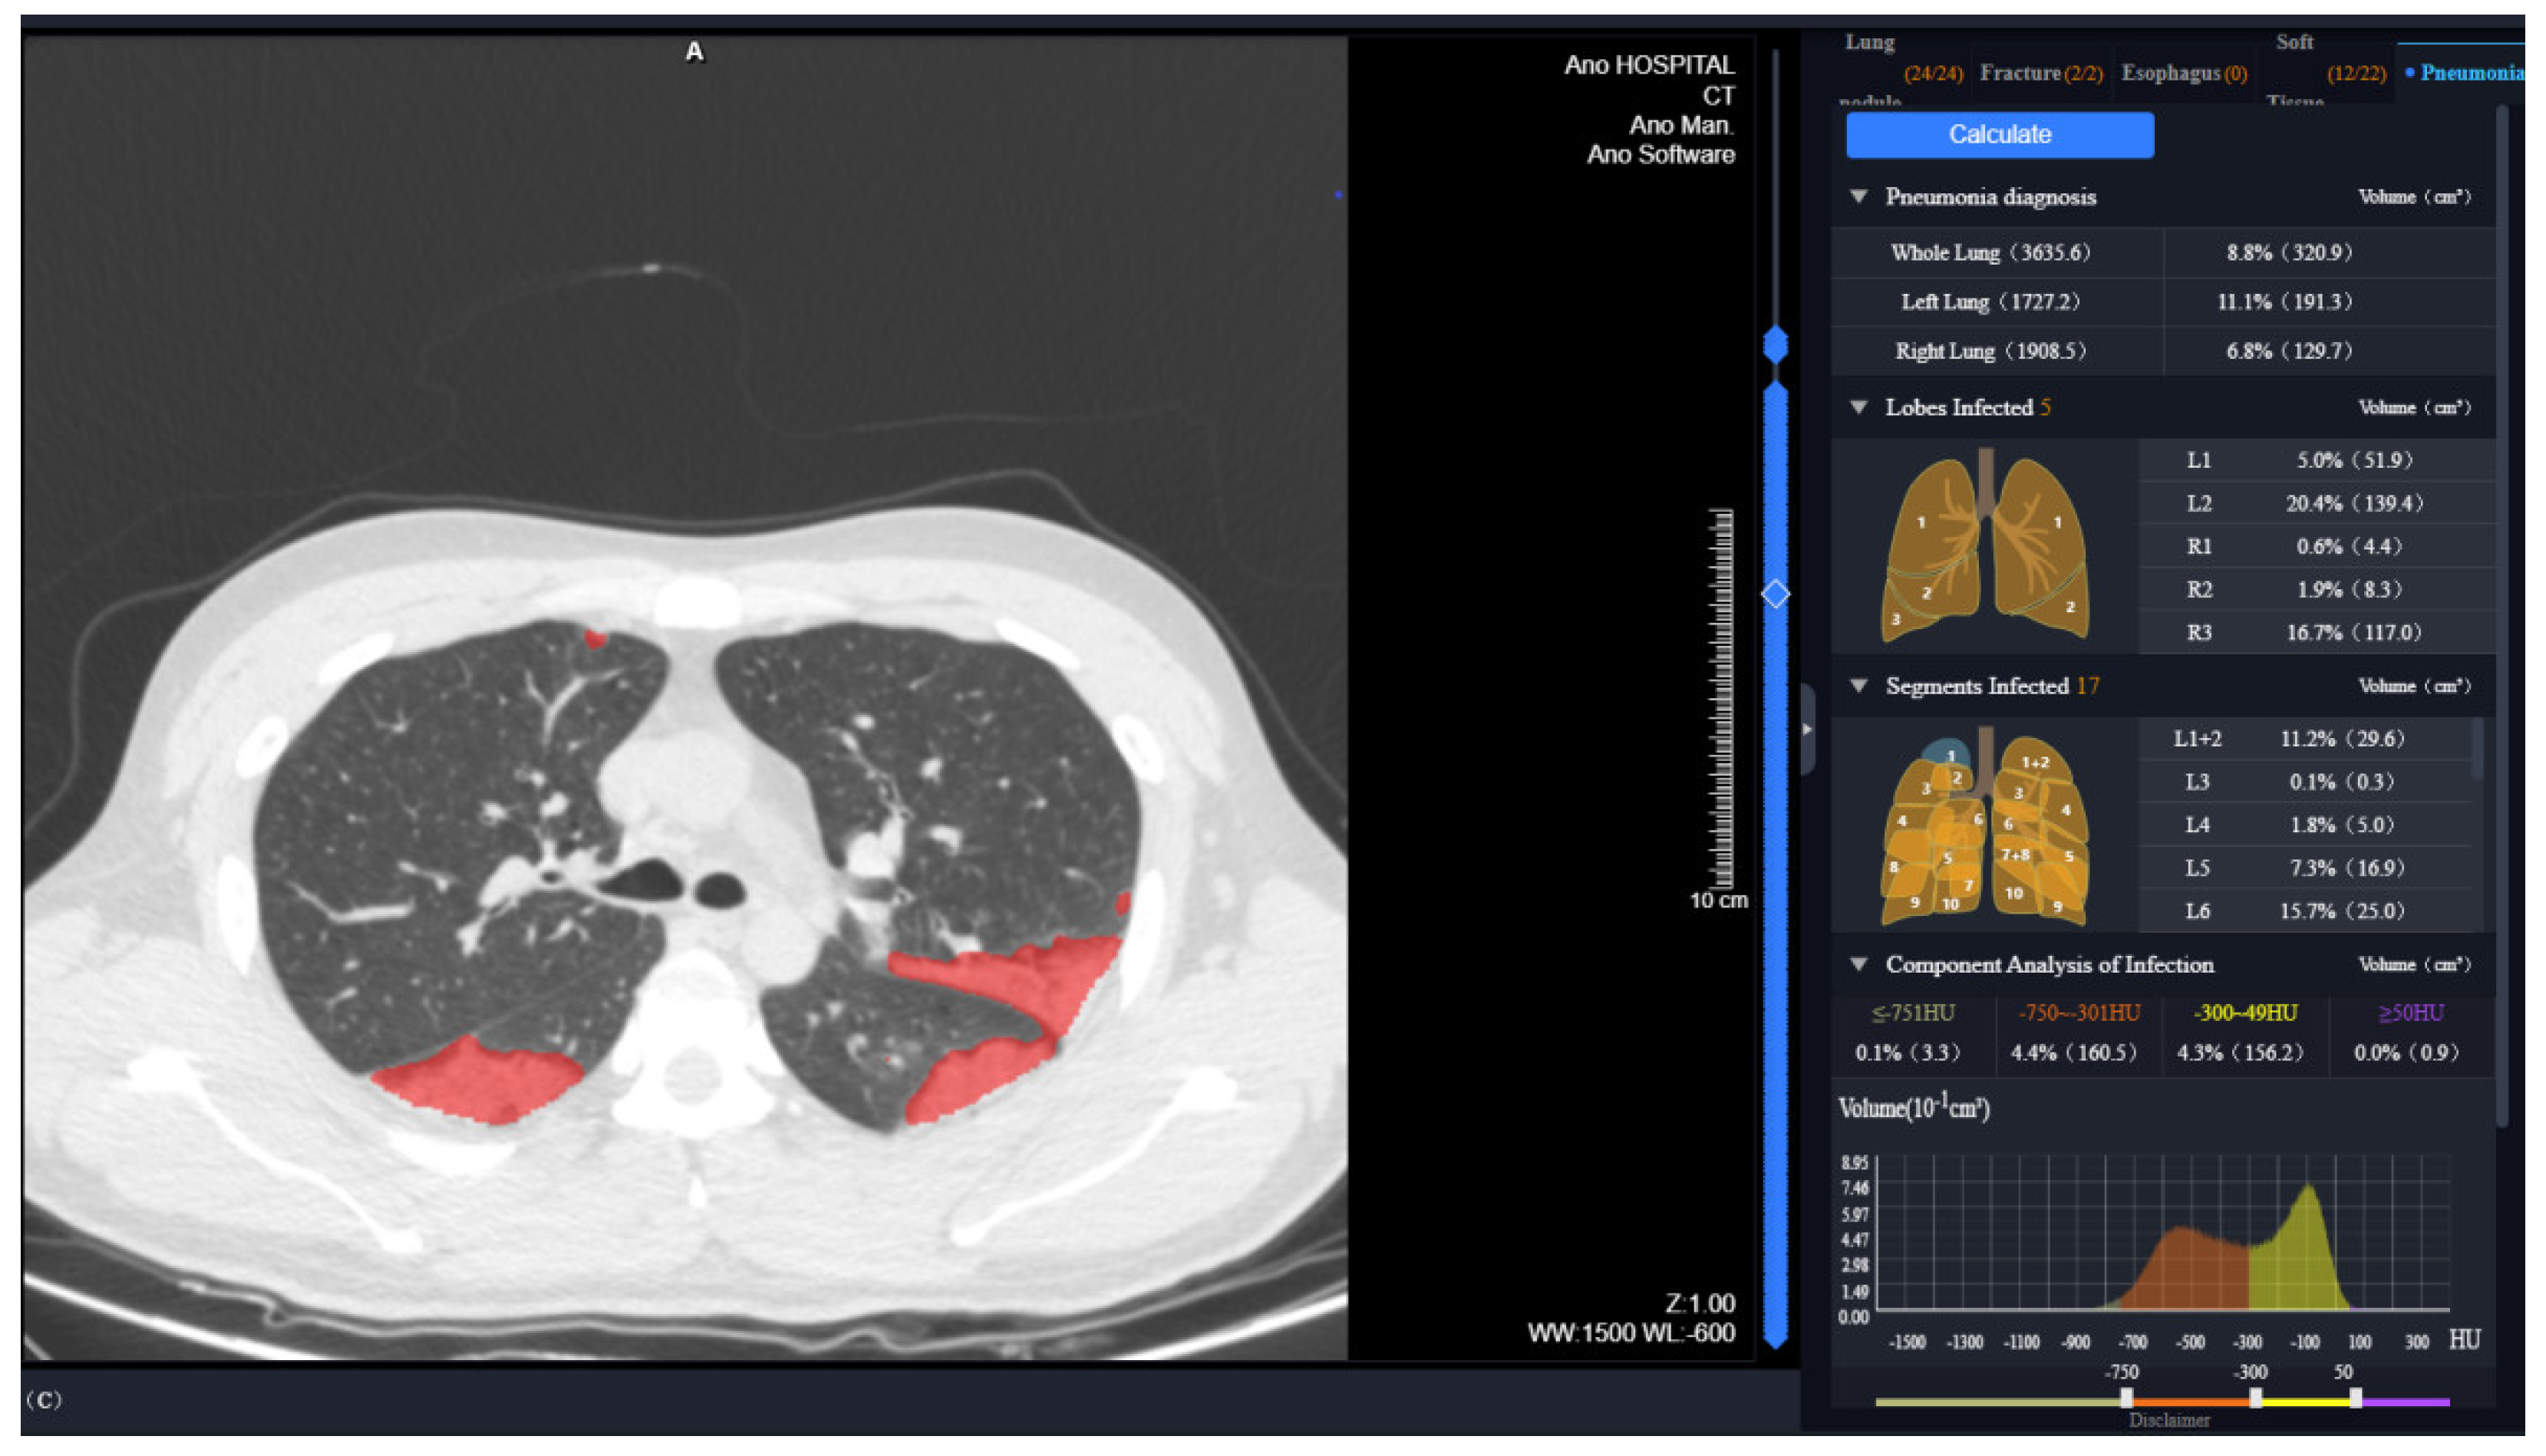

Two radiologists (with 5 and 27 years of experience) recorded the lesion locations present on the CT images at discharge in a consistent manner. Quantitative analysis of the lung and lobar volumes and the lesions was performed on the uAI Intelligent Assistant Analysis System (United Imaging Intelligence), as previously reported [17,21]. Each lobe was automatically segmented by identifying the bilateral lung contours and the interlobular fissures (left oblique fissure, right horizontal and oblique fissure), and the pneumonia lesions were distinguished automatically. Manual correction was performed by one radiologist in case of inaccurate delineation, and rechecked by another radiologist. Well-aerated lung tissue (−950 HU to −750 HU), ground-glass opacity (GGO) lesions (−750 HU to −300 HU), and consolidation lesions (−300 HU to 50 HU) were distinguished based on the CT values [22,23,24]. In total, the following parameters related to the volume and residual lesions in the entire lung and five lobes were measured (Figure 1): (1) mean lung density of total lung tissue (or lobe tissue) (MLD, HU); (2) total lung (or lobar) volume (LV, cm3); (3) well-aerated lung tissue volume (WAL, cm3); (4) mean lung density of lesion (MLDLe, HU); (5) total lung (or lobar) lesion volume (LeV, cm3); (6) GGO volume (GV, cm3); (7) consolidation volume (CV, cm3); (8) percentage of lobar volume to total lung volume (LV%); (9) percentage of LeV to total lung (or lobar) volume (LeV%); (10) percentage of the WAL to total lung (or lobar) volume (WAL%); (11) percentage of GV of the lesion (GV%); and (12) percentage of CV of the lesion (CV%).

Figure 1. Quantitative analysis of CT images at discharge in uAI intelligent assistant system.